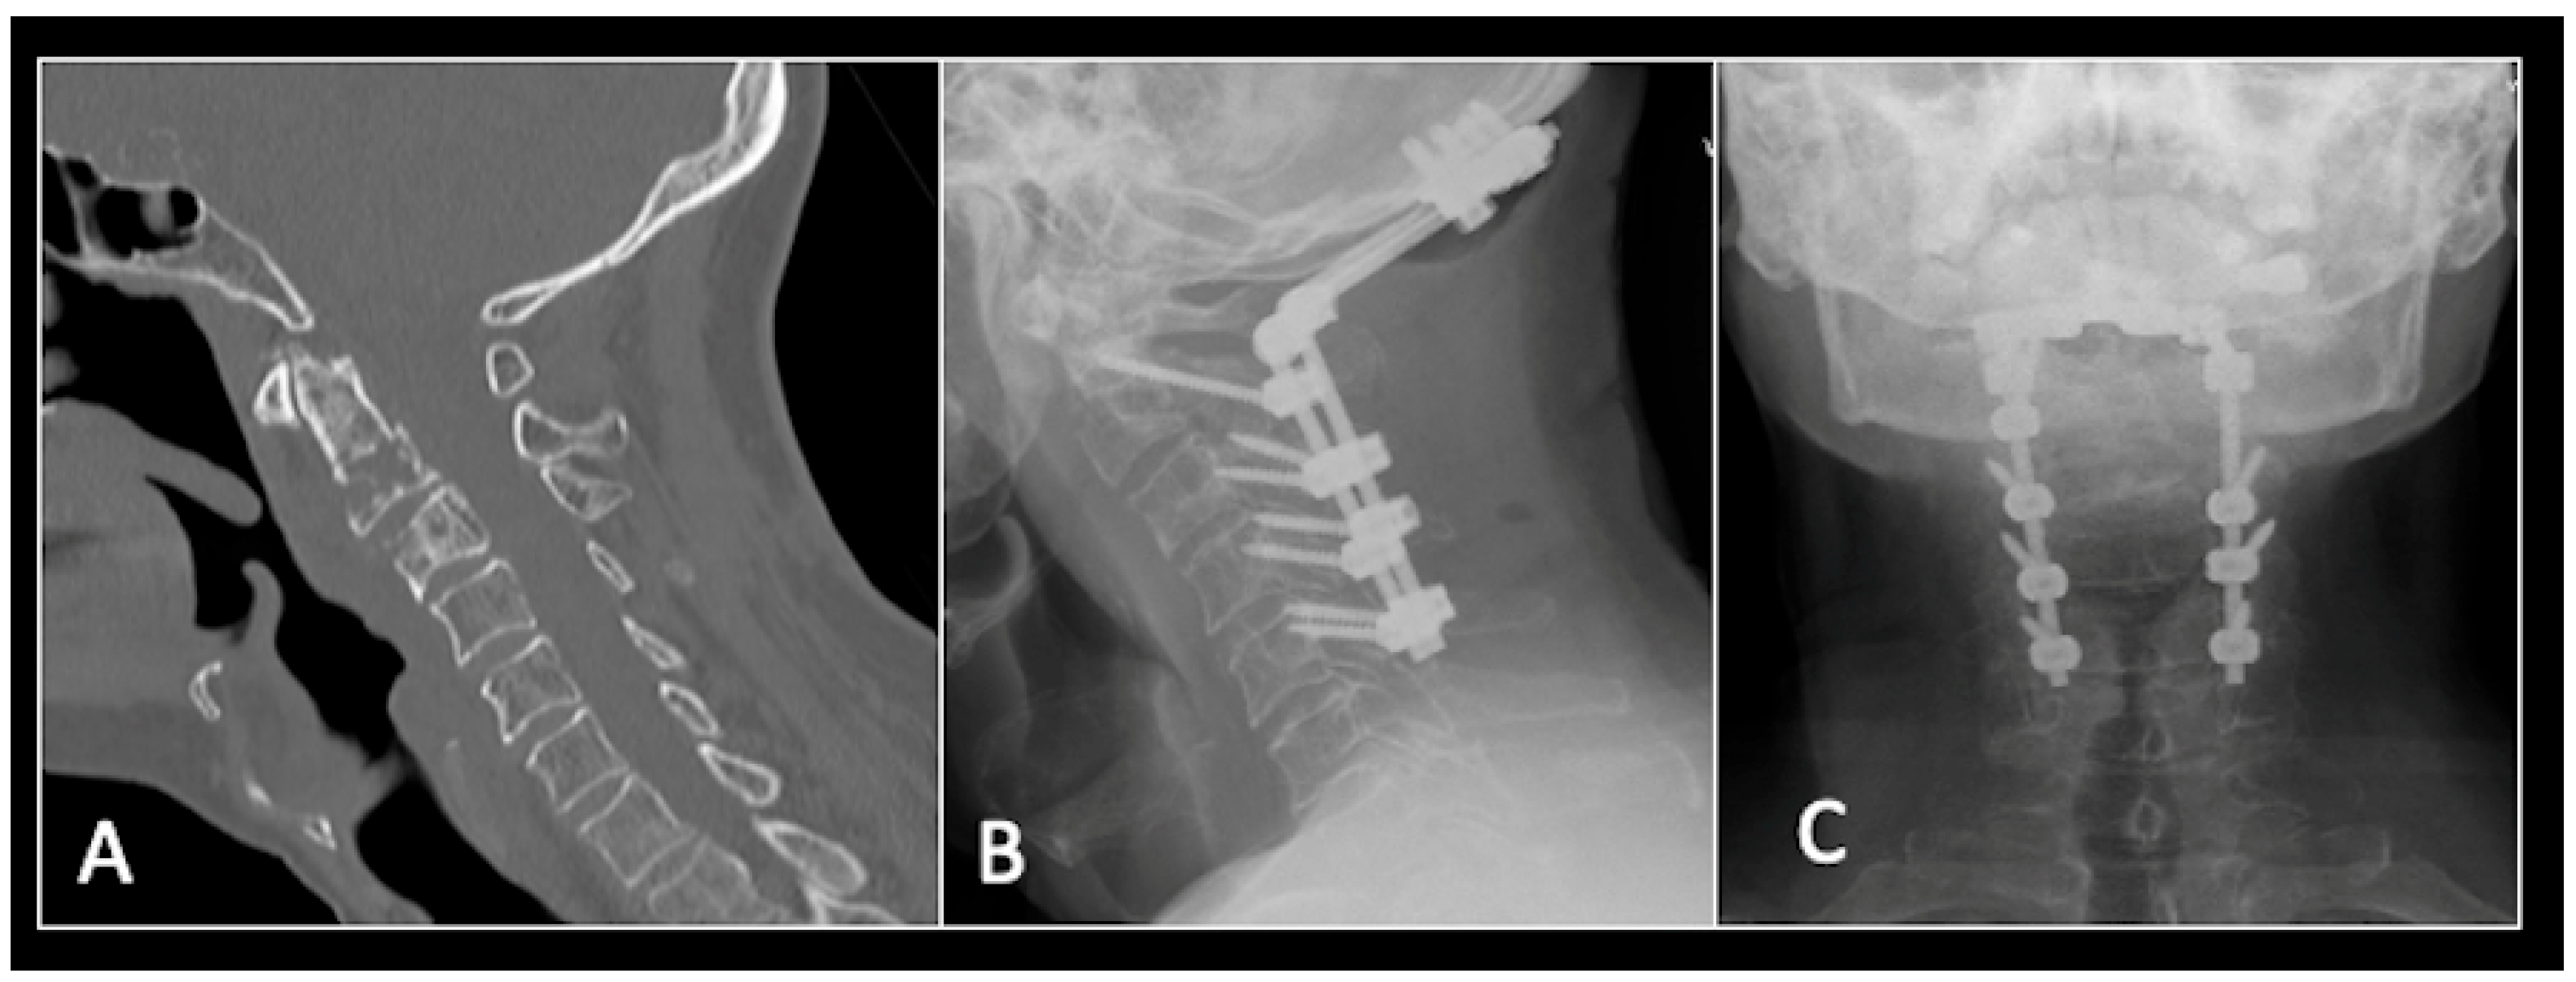

This 68-year-old male was referred to our institution with a 4 cm cervical mass localised to C2/3 following investigations for left-ear congestion and altered hearing (Figure 7). A CT-guided biopsy confirmed a conventional chordoma. The patient underwent separation surgery with adjuvant proton beam therapy. There was no evidence of disease progression on 3-monthly surveillance imaging (Figure 8). Approximately 12 months following separation surgery, the patient presented with acute onset neck pain. A C2 odontoid peg fracture was diagnosed requiring a posterior occipitocervical stabilisation procedure (Figure 9). Pre-stabilisation MRI imaging confirmed no tumour progression (Figure 10).

Figure 9.

(A) Sagittal CT imaging showing pathological fracture of C2 vertebral body. (B,C) Posterior occipitocervical stabilisation on lateral (B) and AP (C) radiographs, respectively.